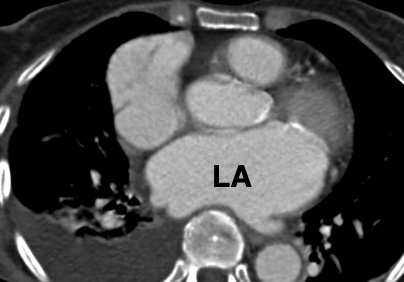

Sténose Mitrale

- Associé virtuellement toujours à un RAA (Rhumatisme Articulaire Aigu = Complication d’Angine à Streptocoques chez les enfants

- Dilatation de l’OG

- VG non atteint

- Hypertension Pulmonaire